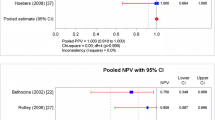

Correlation plot of mean radiation dose (cGy) and the post-treatment increase in Annexin uptake, mean ΔU, in parotid glands (a), normalised for tracer dose and body weight. Circles represent parotid glands treated with IMRT, triangles parotids treated with conventional technique. In b, the correlation between mean radiation dose (cGy) and the post-treatment increase in Annexin uptake, mean ΔU, in submandibular glands is given

In the parotid glands, weak baseline uptake was present in all cases. The post-treatment TAVS showed moderate to strong increase in uptake in 24 of 26 parotid glands (Fig. 2a). The average of the mean number of counts increased from 55 to 88 (p < 0.001). Visual analysis of the increase in uptake showed that these changes were related to the radiation portals and the dose given to the parotid glands (Fig. 3). The difference in Annexin uptake between the post-treatment and baseline TAVS (ΔU) in each parotid gland was correlated with the radiation dose at the time of post-treatment scintigraphy (n = 13 patients, n = 26 parotids). The mean ΔU showed a positive correlation with the mean radiation dose (Pearson coefficient r = 0.59, p = 0.002): parotid glands that received a higher dose of radiation showed a higher Annexin uptake (Fig. 4a). The increase in Annexin uptake in parotid glands that were treated with parotid-sparing IMRT was less than in parotid glands that were treated with a conventional three-field technique (IMRT 29 counts, three-field technique 59 counts, p = 0.02). The given radiation dose at the time of post-treatment TAVS (6 or 8 Gy) and the mode of cisplatin administration (IA or IV) did not affect the uptake in parotid glands. As xerostomia scoring was not documented sufficiently detailed in the files, we interviewed patients alive at last follow-up for xerostomia grading for the purpose of this study. In nine patients alive at last follow-up, the treatment-induced Annexin uptake in parotid glands was related to the subjective xerostomia rating using the EORTC QLQ HN-35 questionnaire [22]. No relation could be established in this small set of patients (data not shown).

For the submandibular glands, a similar pattern as with the parotids was observed: absent/weak baseline uptake and moderate to strong increase after the start of chemoradiation (Fig. 2b). The average of the mean number of counts increased from 85 to 132 (p < 0.001). No correlation between the ΔU and radiation dose was noted (Fig. 4b), probably as all submandibular glands were located within the high-dose region.

The baseline TAVS showed moderate to strong Annexin uptake in the primary tumour in all patients, indicative of spontaneous apoptosis or necrosis. On the post-treatment TAVS, the uptake in tumour clearly increased in nine cases; in the other four, little or no changes occurred (Fig. 2c). The average of the maximum number of counts increased from 127 to 163 (p = 0.007). The difference between post-treatment and baseline TAVS (ΔU) in primary tumour was not correlated with primary tumour volume (Pearson coefficient r = 0.39, p = 0.21) nor with the mode of chemotherapy administration (p = 0.21). In nine patients, 17 lymph node metastases were present in the neck (mean lymph node volume 5 cm3, range 1–19). The treatment-induced Annexin uptake (maximum ΔU) in primary tumour was positively correlated with the uptake in corresponding lymph node metastases (r = 0.73, p = 0.004) as shown in Fig. 5. To verify that the observed effects of Annexin uptake in different structures could not be attributed solely to the administered radioactive dose per patient but was tissue-specific, we calculated the correlation between the ΔU in tumour and parotid glands. No evidence of such an effect was found (r = 0.28, p = 0.18).

Correlation plot of the treatment-induced increase in Annexin uptake, maximum ΔU, in primary tumour and lymph node metastases. Each colour represents an individual patient. Some patients had multiple lymph node metastases originating from the same primary tumour. In these cases, multiple values of treatment-induced Annexin uptake in lymph nodes (on the y-axis) correspond to a single value of the primary tumor (on the x-axis)

Due to the large inter-patient variability in the baseline TAVS (Fig. 2c), the subtraction method for assessing treatment-induced changes was chosen over a relative method (e.g. percentage change). In this figure, it is important to notice that the maximum uptake value of the baseline and post-treatment scan might be located in different points within the tumour ROI. Therefore, these data cannot be simply subtracted, but for the calculation of the maximum ΔU in primary tumour and lymph nodes, the baseline scan was first subtracted from the post-treatment scan, and, subsequently, these parameters were calculated from the subtraction scan. The treatment-induced Annexin uptake in primary tumour and pathological lymph nodes showed a positive correlation: Patients with primary tumours with a high Annexin uptake also appeared to have lymph node metastases with high Annexin uptakes. The ΔU in primary tumour and lymph node metastases showed large inter-patient differences (Fig. 5). This variation could not be attributed to differences in the route of cisplatin administration (intravenous or intra-arterial chemoradiation), nor to the radiation doses given (6 or 8 Gy), nor to the primary tumour volume. This positive correlation for ΔU in primary tumour and lymph nodes as well as the large inter-patient differences might represent a tumour-specific apoptotic response.